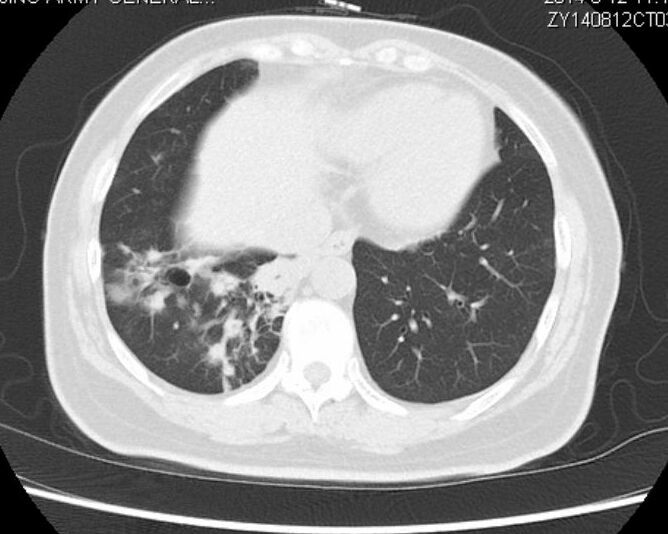

以下是第50个月的时候复查:

与两年前对比,病灶有所增大,但未影响肺功能,老太太总体状态很不错!

该患者在确诊时已经属于肺癌晚期伴有多发转移,最后一次随访时,已经带瘤生存50个月。

这是一个奇迹!